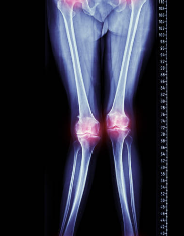

비타민d 구루병

비타민 D 결핍은 골다공증, 골연화증, 골절 등 뼈 건강에 문제를 일으키는 질환과 관련이 있습니다. 그리고 비타민 D 결핍으로 인해 발생하는 골병 중에 하나가 구루병입니다.

구루병은 뼈의 염증과 골감소, 그리고 골 조직이 변성되는 질환으로, 비타민 D 결핍이 가장 일반적인 원인 중 하나입니다. 구루병은 일반적으로 노인에서 발생하는데, 나이가 들면 피부에서 비타민 D가 합성되는 능력이 저하되기 때문입니다. 또한, 비타민 D를 충분히 섭취하지 못하는 식습관이나 지역적인 문제 등도 구루병 발생 위험을 높일 수 있습니다.

구루병은 주로 다리 뼈나 골반 부위에서 발생하는 통증과 함께 보행 불편, 근육 약화, 골절 등의 증상을 유발합니다. 구루병은 비타민 D 결핍을 예방하고 치료함으로써 예방할 수 있습니다.